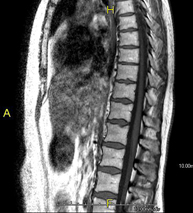

- Thoracic spine MRI

This non-invasive diagnostic procedure uses an electromagnetic field and radio waves (from a transmitter and receiver) to acquire high-definition anatomical images of the thoracic spine. It is a radiation-free procedure. Indicated for: trauma, degenerative problems, hernias, tumours.

- Thoracic + lumbar spine MRI

This non-invasive diagnostic procedure uses an electromagnetic field and radio waves (from a transmitter and receiver) to acquire high-definition anatomical images of the thoracic and lumbar spine. It is a radiation-free procedure. Indicated for: trauma, spinal degeneration, hernias.

A non-invasive diagnostic test that involves obtaining high-definition anatomical images of the thoracic and lumbar spine using an electromagnetic field and radio waves (with transmitter and receiver). It is a radiation-free procedure. Indicated for: trauma, spinal degeneration, hernias.